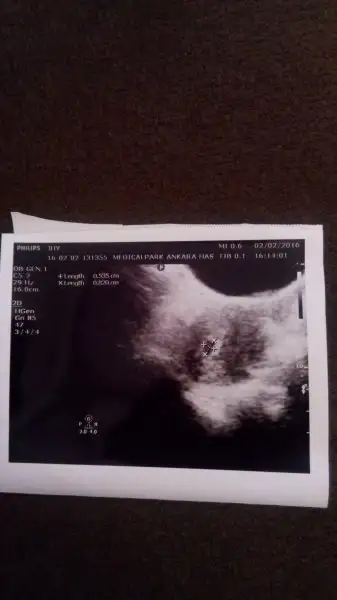

Keseyi gördüğümde 4+6 idi canım. Üstten gördü doktor. İlk çocuğumda bu haftada üstten görememişti. Vajinal ultrasonda görmüştük. Değişkenlik gösteriyor demek ki. Kalp atışı 6+ haftada görünüyor ama en net 8 haftalıkken duyuluyor diye biliyorum. Sabırlı olmakta fayda var. :)

4,5 5 dedi net birşey söylemedi :) bende görüyüor mu diye bakıp duruyorum boyuna da 8 mm dediCanım sende görünmüyor. Haftası ve gününü çekmemiş. Sadece boyu görünüyor. Doktorun söylemedi mi kaç haftalık göründüğünü?

Canım ben bugün gittim doktora tam 5+0 ım karından baktı kese görünmedi vajinal bakmayalım haftaya karından bakarız dedi doktorkızlar keseyi ve kalp atışını gören var mı? kaç hafta kaç günlükken gördünüz? Vajinal mi karından ultrasonla gördünüz? pzt randevu var ama sanırım sadece kese için çağırdı. kalp atışı diğer hafta dedi. Çatlayacam meraktan stresten ya.